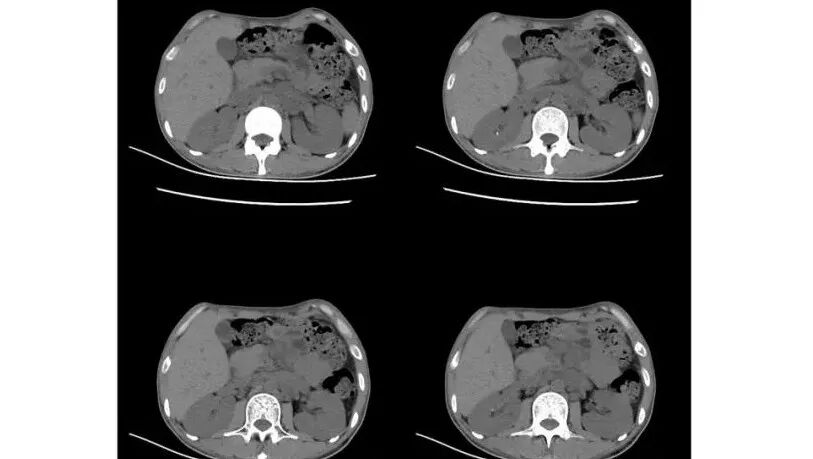

以下为2021-7-15日上腹部CT

影像与临床:1.青年男性,HlV阳性,颜面部皮疹(未提供皮疹图像)、发热(高热),实验室CRP、PCT高,T-Spot阴性。2.右肺下叶空洞结节,壁厚不均,边界清楚,其内线状影,未见液平及钙化,未见卫星灶,纵隔淋巴结增大,双侧腋窝见增大淋巴结。心腔内低密度提示贫血可能。肝脾影增大,未见结节影及块影。腹膜后见多发增大淋巴结。

综合分析:本例肺部影像学改变并不具有特征性,空洞性病灶须与多种疾病鉴别,但年轻HIV阳性患者,高热,皮疹,肝脾增大,纵隔、腋窝、腹膜后见多发增大淋巴结等都强烈提示马尔尼菲篮状菌感染的可能性。